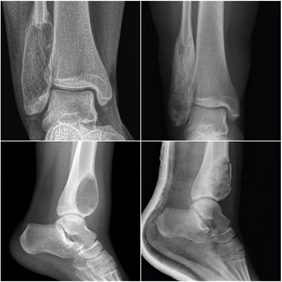

Siempre debemos estar atentos a los síntomas que nos refieren los pacientes, el tiempo de evolución y la respuesta a los tratamientos realizados. En los estudios de radiografías debemos igualmente observar con detenimiento cualquier alteración del hueso que se diferencie de los patrones radiológicos normales, con fin de detectar las anomalías óseas e iniciar el estudio y los tratamientos de una forma precoz y adecuada, muchas veces junto a un equipo multidisciplinar. En las radiografías debemos prestar atención a la localización de la lesión, su forma, tamaño, matriz ósea, la existencia de reacción perióstica o afectación de partes blandas.

El quiste óseo aneurismático, aunque es un tumor benigno, es localmente agresivo. Constituye alrededor del 2% de los tumores benignos del hueso en menores de 20 años. En las radiografías se suele observar una lesión lítica y expansiva con elevación del periostio y en ocasiones márgenes mal definidos que recuerdan a una lesión maligna, por lo que podría precisar biopsia y análisis anatomopatológico en algunos casos. La fractura patológica se produce hasta en el 30% de los casos, precisando estabilización quirúrgica en caso de fracturas desplazadas y tratamiento específico con aporte de injerto óseo para su tratamiento definitivo.

El tumor de células gigantes es una lesión tumoral benigna pero localmente agresiva. Provoca lesiones líticas expansivas que se localizan fundamentalmente en las metáfisis y epífisis de huesos largos. La edad de aparición está entre los 20 y 50 años y se suele localizar con mayor frecuencia en la zona cercana a la rodilla, en la epífisis distal del fémur, en la tibia proximal y en el radio distal. Se describe la presencia de metástasis pulmonares en casi el 5% de los pacientes. Habitualmente el paciente refiere una historia de dolor persistente en torno a la rodilla, con afectación progresiva de la funcionalidad. Las fracturas patológicas suelen aparecer fundamentalmente en casos avanzados, con gran debilidad cortical. En la rodilla puede asociar derrame articular y fracturas osteocondrales por debilidad del hueso subcondral.